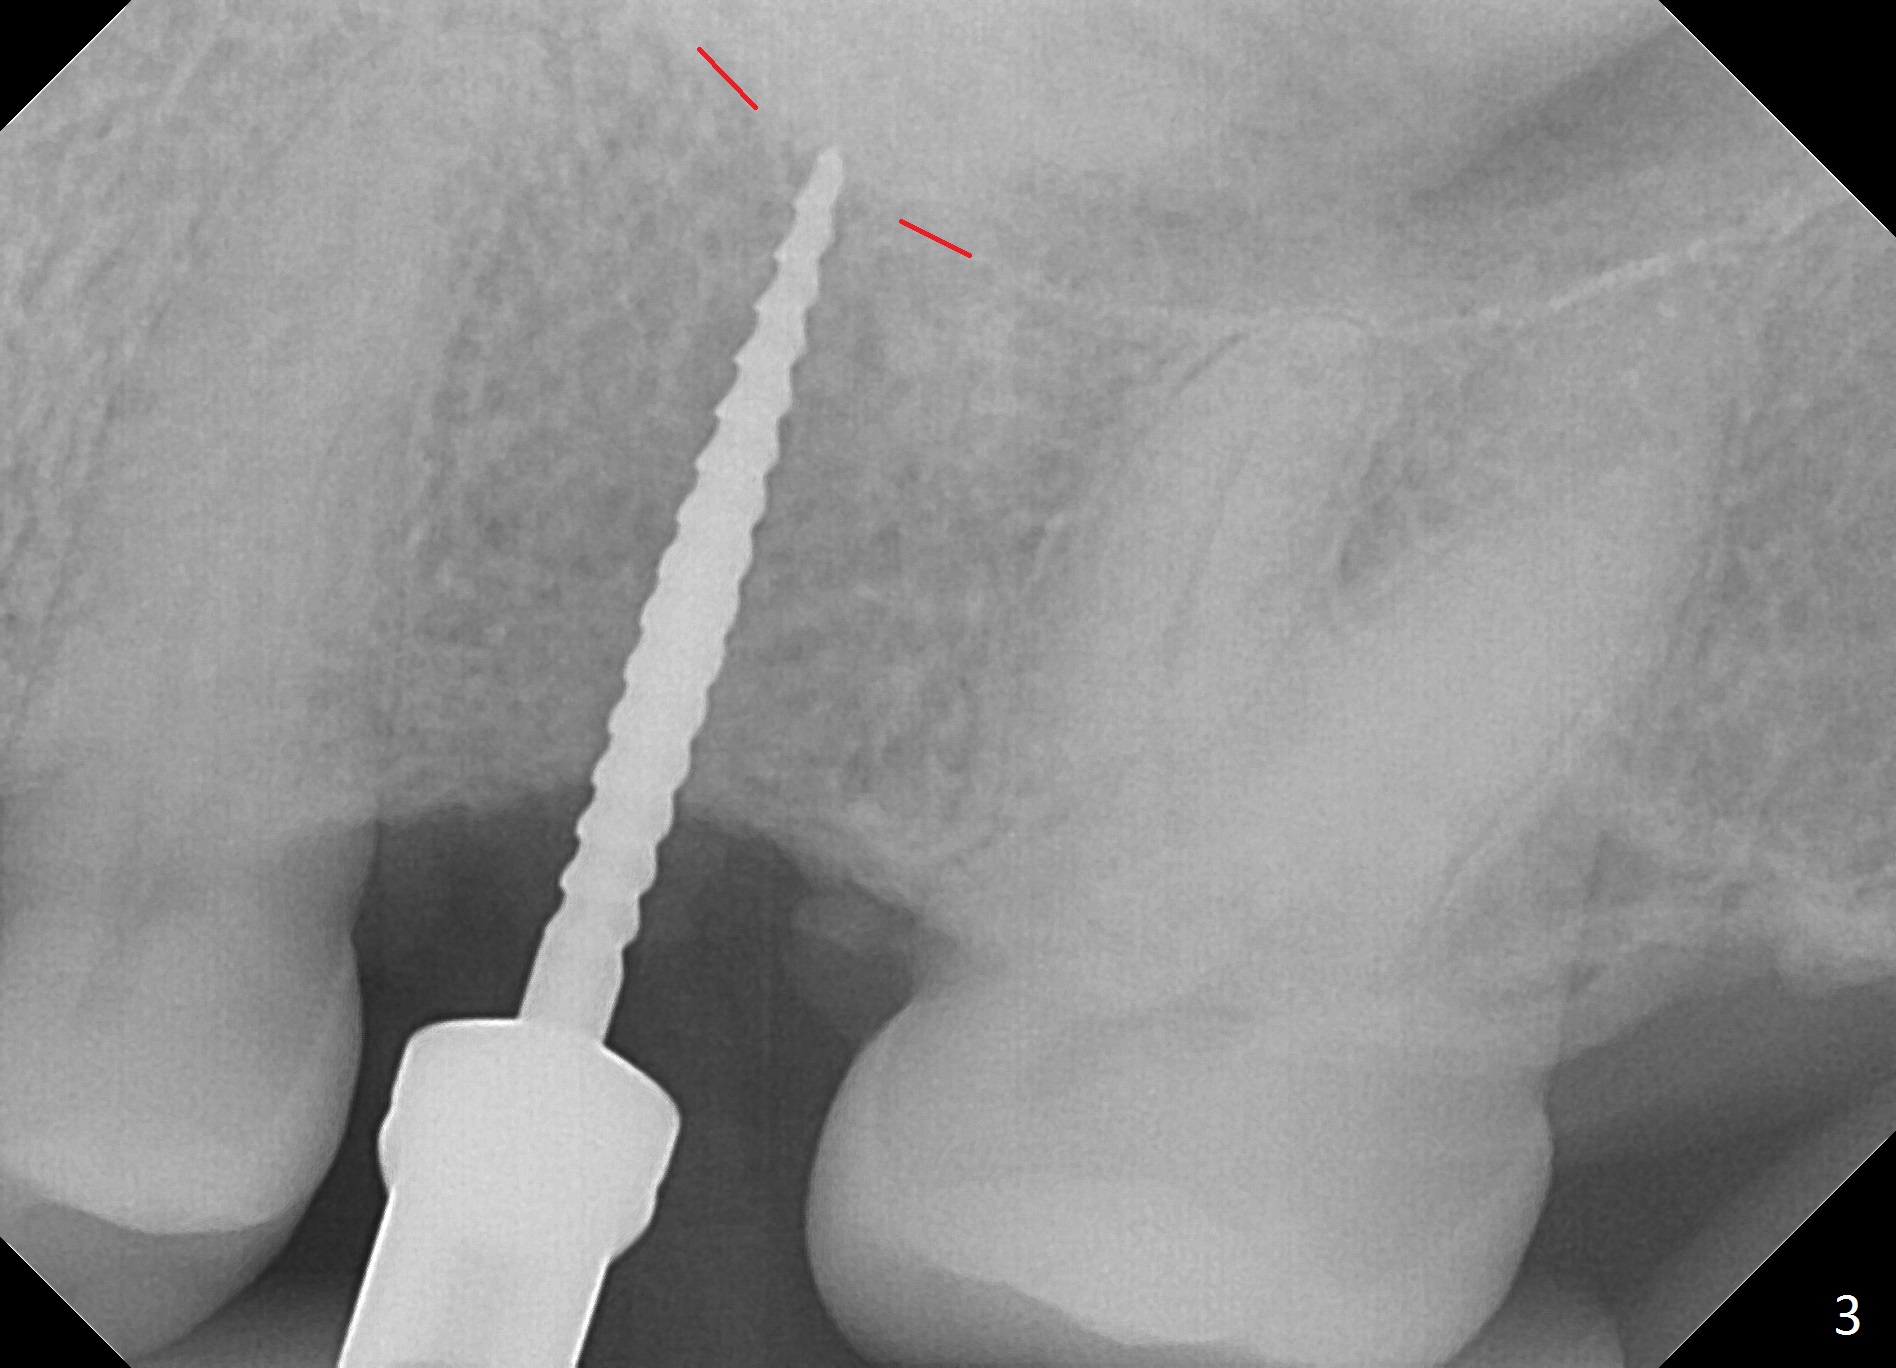

The edentulous area at #14 is moderately atrophic, After incision, the bone is too hard for #15 blade for bone expansion. Osteotomy is initiated with 1.2 mm drill, followed by insertion 1.3/2.3 mm bone expander (Fig.1). Use the same instruments are reused twice to change the trajectory (Fig.2,3). Finally Lindamann bur is utilized to move the osteotomy distally by ~ 2 mm; bone expansion continues until 2.4/3.7 mm expander for 13 mm with 50 Ncm (Fig.4). The last expander 3/4.4 mm barely enters the osteotomy for 6 mm. A 3.7 mm drill has to be used for 12 mm before placement of a 4.5x11.5 mm implant with >35 Ncm (Fig.5). A 5.5x5(3) mm abutment is placed with allograft (<) placed around the implant. Following suturing, periodontal dressing is applied around the implant. The abutment dislodges 3 months postop (Fig.6). Crown is delivered 3 weeks later. The abutment screw is retightened ~ 2 months later. He is a bruxer. The abutment screw is loose again <2 years post cementation (6 months post #18 screw retightenting and occlusal reduction), probably related to distal implant placement (Fig.7).